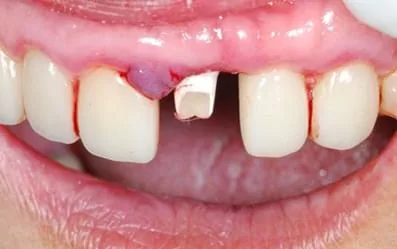

採取無創傷性拔牙,看到牙根確實已斷裂

不翻瓣微創植牙:植入前檢查植體角度,再依理想位置植入Biomet 3i植體

裝上臨時柱心,不傷害鄰牙全瓷冠

不需戴活動假牙,馬上擁有固定臨時牙套